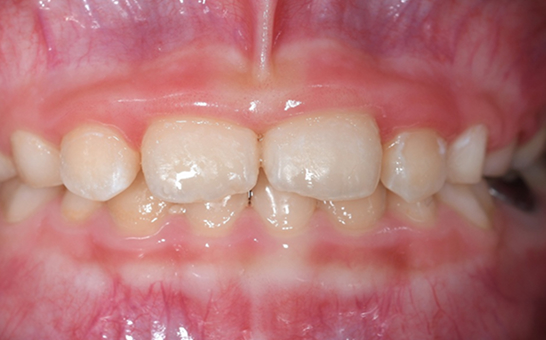

인비절라인 퍼스트(Invisalign First)는 어린이와

성장기 청소년을 위한 투명 교정 장치로, 치아와 턱뼈가

성장하는 과정에 맞춰 설계된 교정 시스템입니다.

해당하는 증상이 있다면 전문의와 상담 후 조기 교정 시

성장기 어린이에게 교합이 틀어지는것을 미리 예방 할 수 있습니다.

영구치가 나오는 과정에서

공간이 부족한 어린이

앞니의 심한 돌출이나

비대칭으로 인한 기능적

문제가 있는 어린이

턱 성장에 맞춰

치아 교정이 필요한 경우

기존 금속 교정 장치가

부담스러운 어린이와 부모님

※ 바른선택치과의원은 의료법을 준수하며 위 케이스는 실제 내원 환자분의 동의하에 공개된 사진과 동일한 환자분께 같은 조건에서 촬영한 사진을 활용했습니다.

개인에 따라 진료 및 치료 방법이 다르게 적용할 수 있으며, 효과와 부작용이 개인마다 다르게 나타날 수 있는 점을 안내해 드리며, 진료 전 전문의료진과 충분한 상담을 권해드립니다.